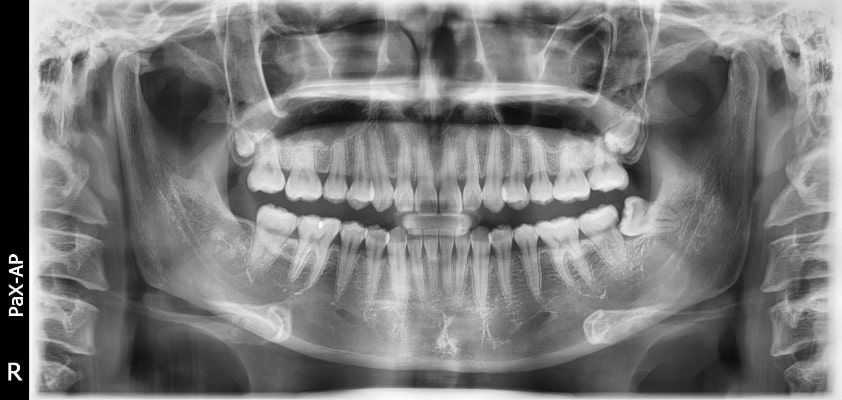

El innovador FOV proporciona un volumen en forma de arco que muestra una vista más amplia de la dentición en comparación con otros dispositivos del mismo FOV.

Normalmente, una imagen de 10x8.5 muestra el diente No.8. Sin embargo, cuando los terceros molares están tumbados sobre su lado hay una gran posibilidad de que el diente se corte de la imagen.

El “volumen en forma de arco” elimina esta posibilidad y muestra el área de dentición oculto.